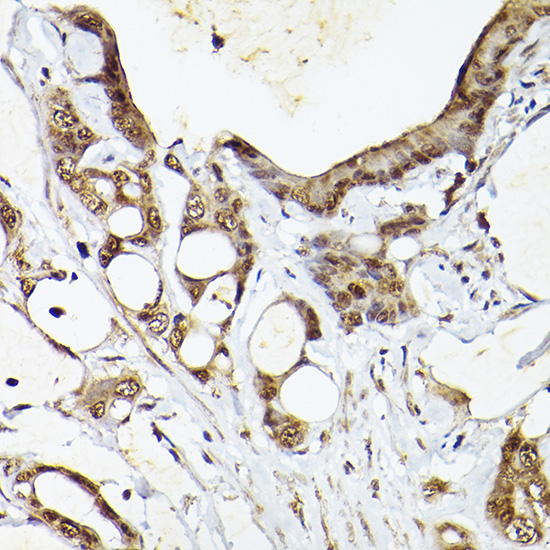

Immunohistochemistry of paraffin-embedded human colon carcinoma using UBQLN4 Rabbit pAb.